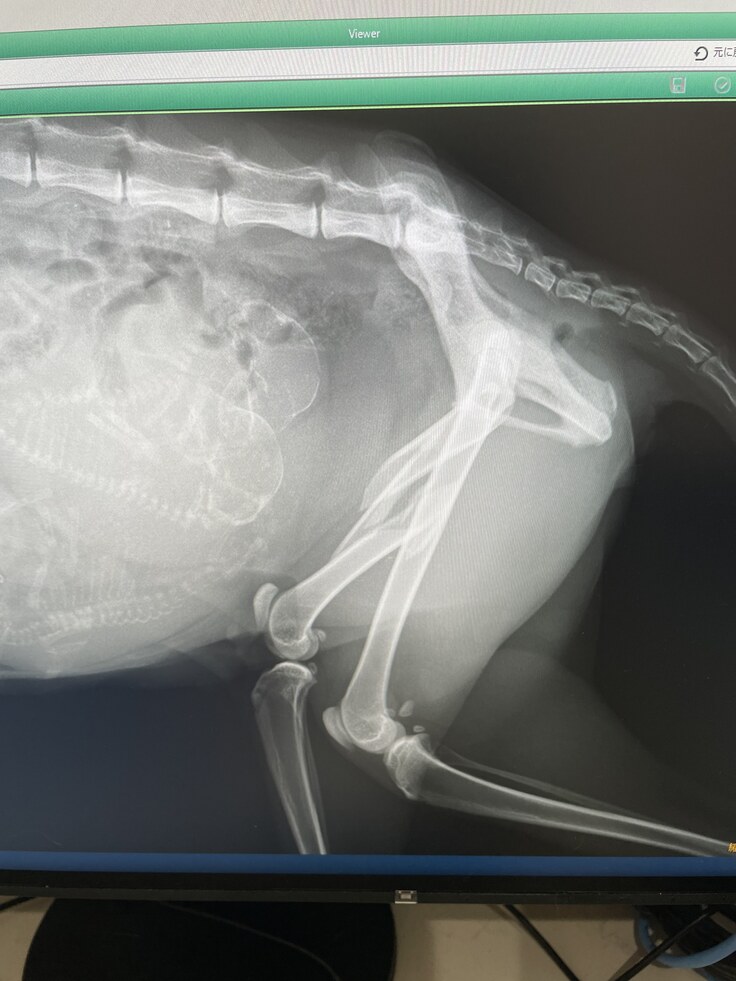

急いで病院へ連れて行ったところ・・・

先生「太ももの骨が3か所骨折してます。2か所は自然にくっつくと思いますが、

1か所は大きくずれて骨折している為自然にくっつくのが難しいと思います。」

と言われました。

先生「治す為には、手術が必要です。手術をしない選択をした場合、今後太ももから

骨折した骨が飛び出てくる可能性があります。」

先生「後、お腹に赤ちゃんが3匹程います。心拍確認もできたので、大きさ的に2日~1週間

程で産まれます。」

●治療・手術内容

大腿骨の骨折3か所の手術、治療代。

妊娠している為、出産後に骨折の手術、体力回復後去勢手術を行う。